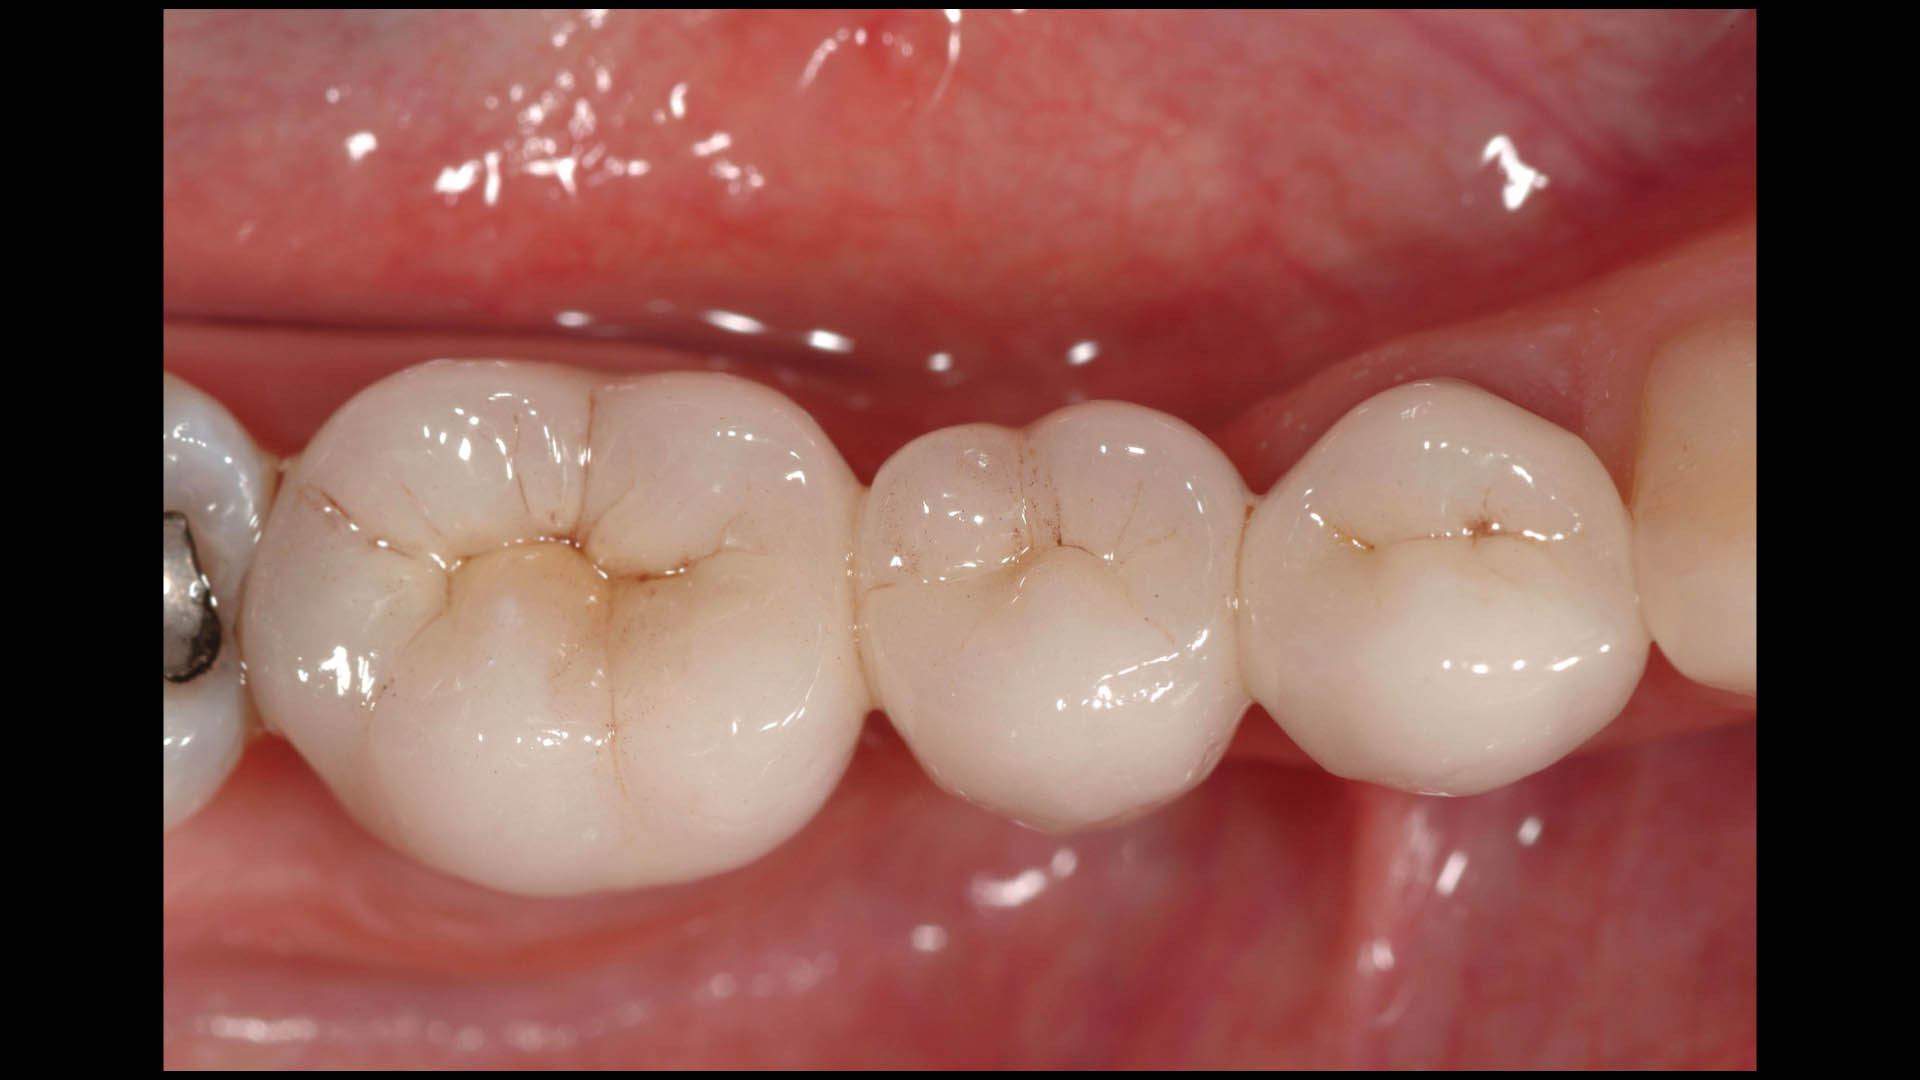

Take a glimpse into the magic of Coral Gables Dentistry through our before and after pictures. See firsthand the incredible smile makeover transformations that have brought confidence and joy to our patients.